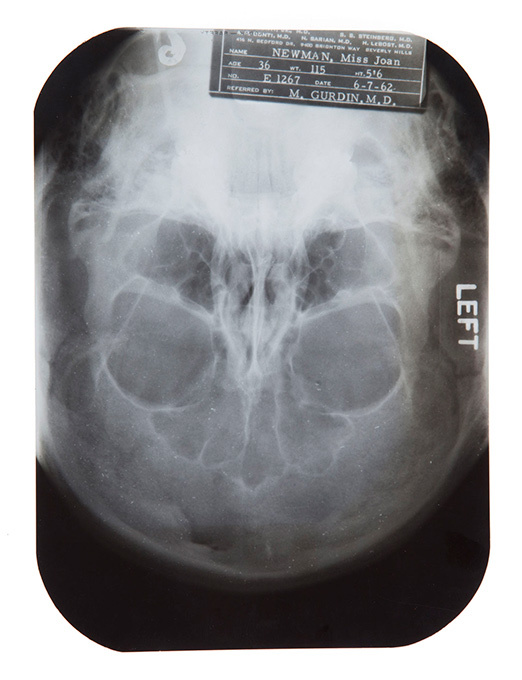

Организаторы Julien's Auctions хотят раскрыть одну из самых главных тайн Голливуда. Медицинский архив содержит рентгеновские снимки и записи врачей, у которых наблюдалась голливудская звезда.

В пресс-релизе события говорится об операциях по коррекции формы носа и подбородка Мэрилин.